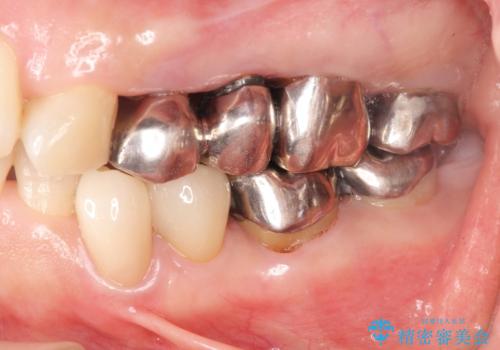

[メタルフリー] 虫歯・銀歯だらけの口腔内を全顎治療

![[メタルフリー] 虫歯・銀歯だらけの口腔内を全顎治療の症例 治療前](https://seimitsushinbi.jp/wp/wp-content/uploads/2025/03/e26a9887bc6905a2f0f51f5772b5ac9c-500x350.jpg?v=1741918285)